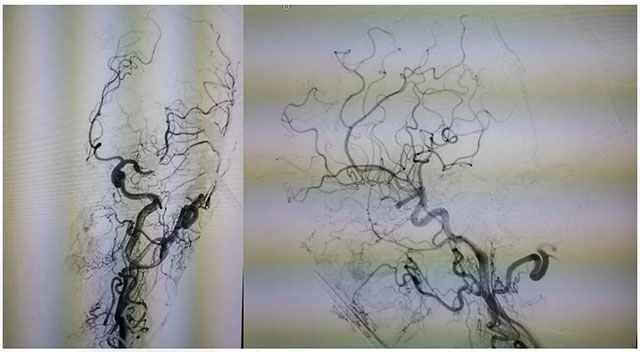

經(jīng)左側(cè)股動(dòng)脈以單彎造影管超選至左側(cè)頸總動(dòng)脈造影明確靜脈穿刺點(diǎn)入路,予以穿刺針穿刺成功后造影明確在位,隨后 Echelon 10微導(dǎo)管到位橫竇,填入一枚彈簧圈做塞子,造影明確位置后,緩慢注入 Onxy18膠 5毫升,鑄膠彌散良好,通過靜脈逆向彌散至部分供血?jiǎng)用}內(nèi)。復(fù)查造影,見瘺口完全被栓塞,引流靜脈消失,手術(shù)成功。

術(shù)后患者臨床癥狀消除,精神矍鑠,現(xiàn)正在康復(fù)中。

▲ 術(shù)后影像